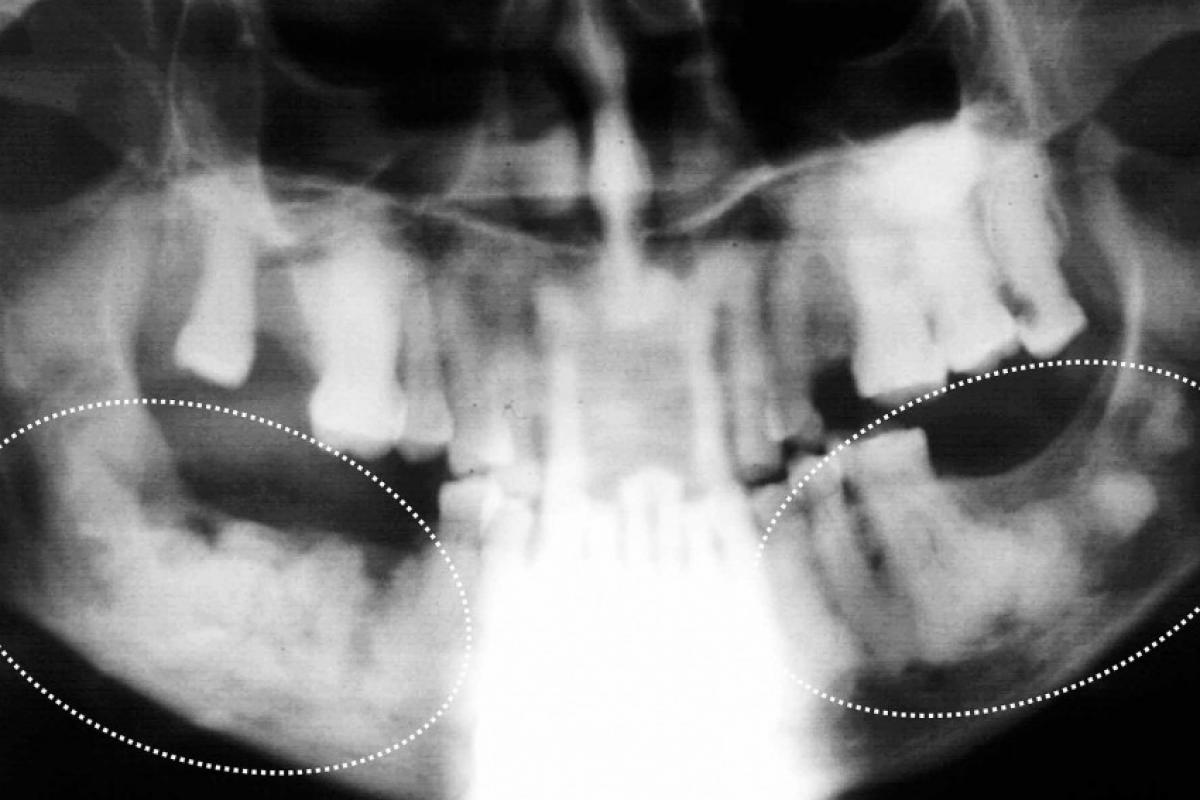

A defesa dos ossos depende do trabeculado. Menos denso, com muitos vasos e células entre as trabéculas, a inflamação chega com células eficientes e em quantidade, assim como mediadores e enzimas, para eliminar as bactérias invasoras. Este quadro vai se chamar osteíte focal.

Quando o osso é muito denso, terá poucos e pequenos espaços medulares para conter os vasos e uma mínima quantidade de células inflamatórias e mediadores. A inflamação prolonga-se e os tecidos medulares sucumbem por compressão dos vasos, e as bactérias tomam conta.

Em pacientes com doenças sistêmicas como diabete não controlado, doença autoimune, desnutrição, oncológicos e outros, o que seria uma osteíte focal, passa a ser uma osteomielite, uma doença inflamatória que se espraia pelo osso vizinho formando pus e fístulas cheias de bactérias.

Muitos pacientes com osso denso e desorganizado na mandíbula tem a Displasia Cemento Óssea Florida, muito comum entre nós. Neles, qualquer causa discreta, leva a uma osteomielite superposta com pus e fístulas. Nos maxilares, áreas esclerosantes indefinidas e bilaterais, sem fístulas, geralmente é Displasia Cemento Óssea Florida e não são lesões induzidas por agentes reabsortivos.

Osteomielites maxilares ocorrem em pacientes: 1-Debilitados por alguma doença sistêmica não controlada, incluindo os que tomam bisfosfonatos. 2-Ou com escleroses ósseas generalizadas e bilaterais da Displasia Cemento Óssea Florida que evoluem para osteomielite superposta.